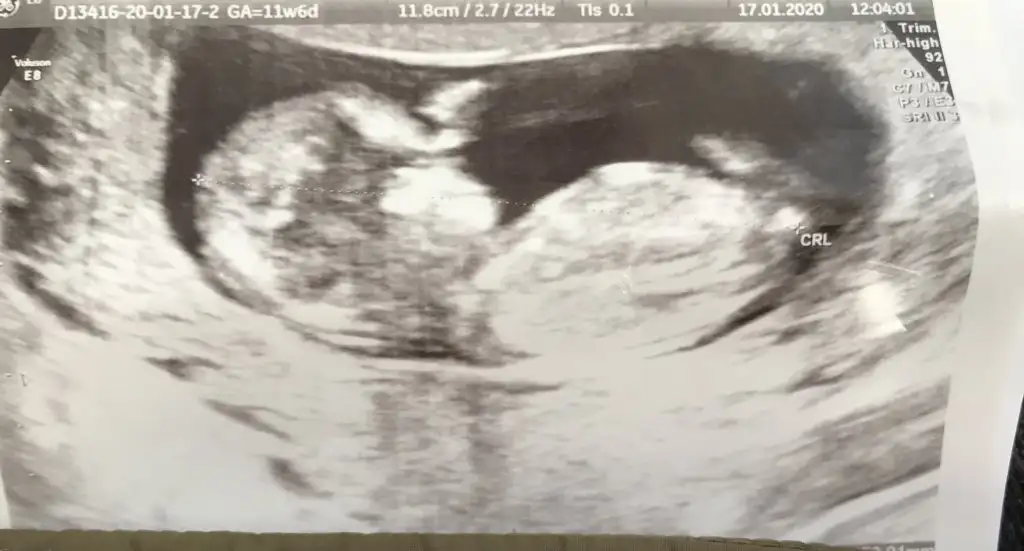

11+6 yorumlarsan sevinirim 😂bu arada doktor birşey söyledi ama net değil.

Benim de 11+6 😍🧿 bana da yorum yapar mısın? Ikra meyra Ikra meyra